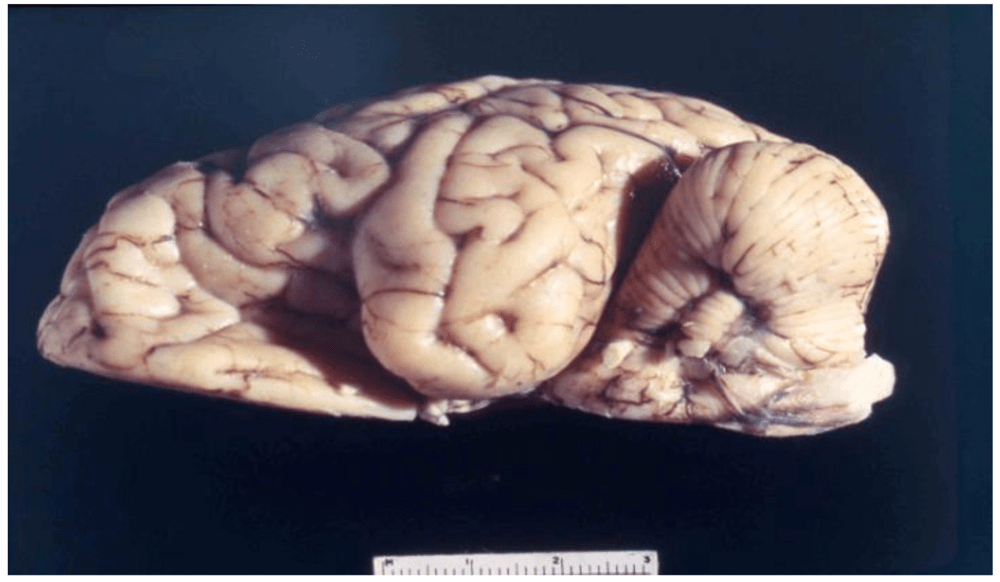

Como os conté en el especial “Lo Macabro”, la tribu Fore es uno de los grupos humanos que se resistía a abandonar los rituales caníbales heredados de los primeros homínidos, y cuando Zigas y Gajdusek llegaron a Papúa, aún era habitual que se comieran porciones de sus familiares muertos en rituales de duelo, incluido el tejido cerebral, consumido principalmente por mujeres y niños. Comer cerebros humanos cual zombis les estaba pasando factura, pues la enfermedad era más prevalente en estos dos grupos de población.

Aunque el canibalismo cesó poco después, aún hubo casos de kuru entre los Fore durante años, ya que la enfermedad tenía un periodo de incubación muy largo, ¡incluso de medio siglo! Y si hablo de periodo de incubación estoy dando a entender que la enfermedad es, en efecto, infecciosa. Gajdusek quiso probarlo y para ello se llevó tejido cerebral infectado a su laboratorio y lo inyectó en chimpancés.